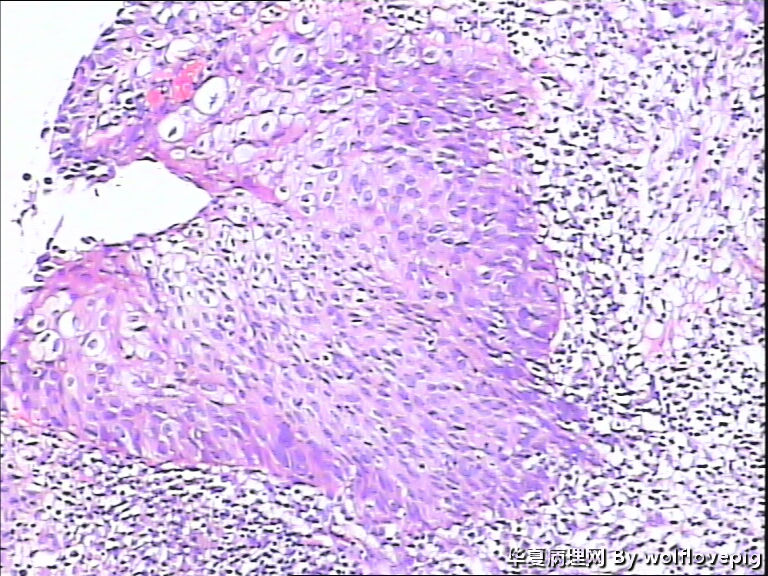

求助,宫颈!

37y

CIN3累腺

CINIII累及腺体

同意CINIII累及腺体

CIN-II 累及腺体。我看不够原位癌。学习了!

CIN2-3,累腺